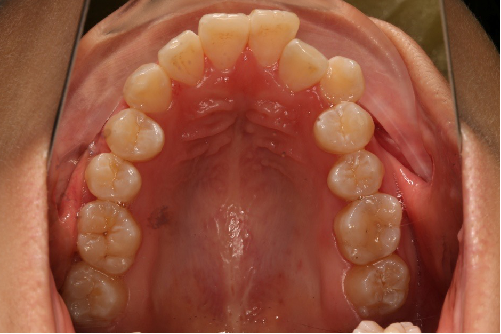

2018.11.14  术后磨牙尖牙I类关系,中线齐,覆合,覆盖正常

牙根基本平行,未见牙根吸收

10 M after Post-Tx

10 M after Post-Tr

2019.08.06  术后  10个月复查

迷你观评价:上下牙齿中线与面中线对齐,笑弧协调,微笑时牙龈暴露量正常,微笑时横向正常,左右唇基本对称。

微观评价:牙齿整齐,咬合关系良好,上下前牙转矩及突度控制良好,磨牙关系I类,尖窝咬合关系良好,OB,OJ正常。